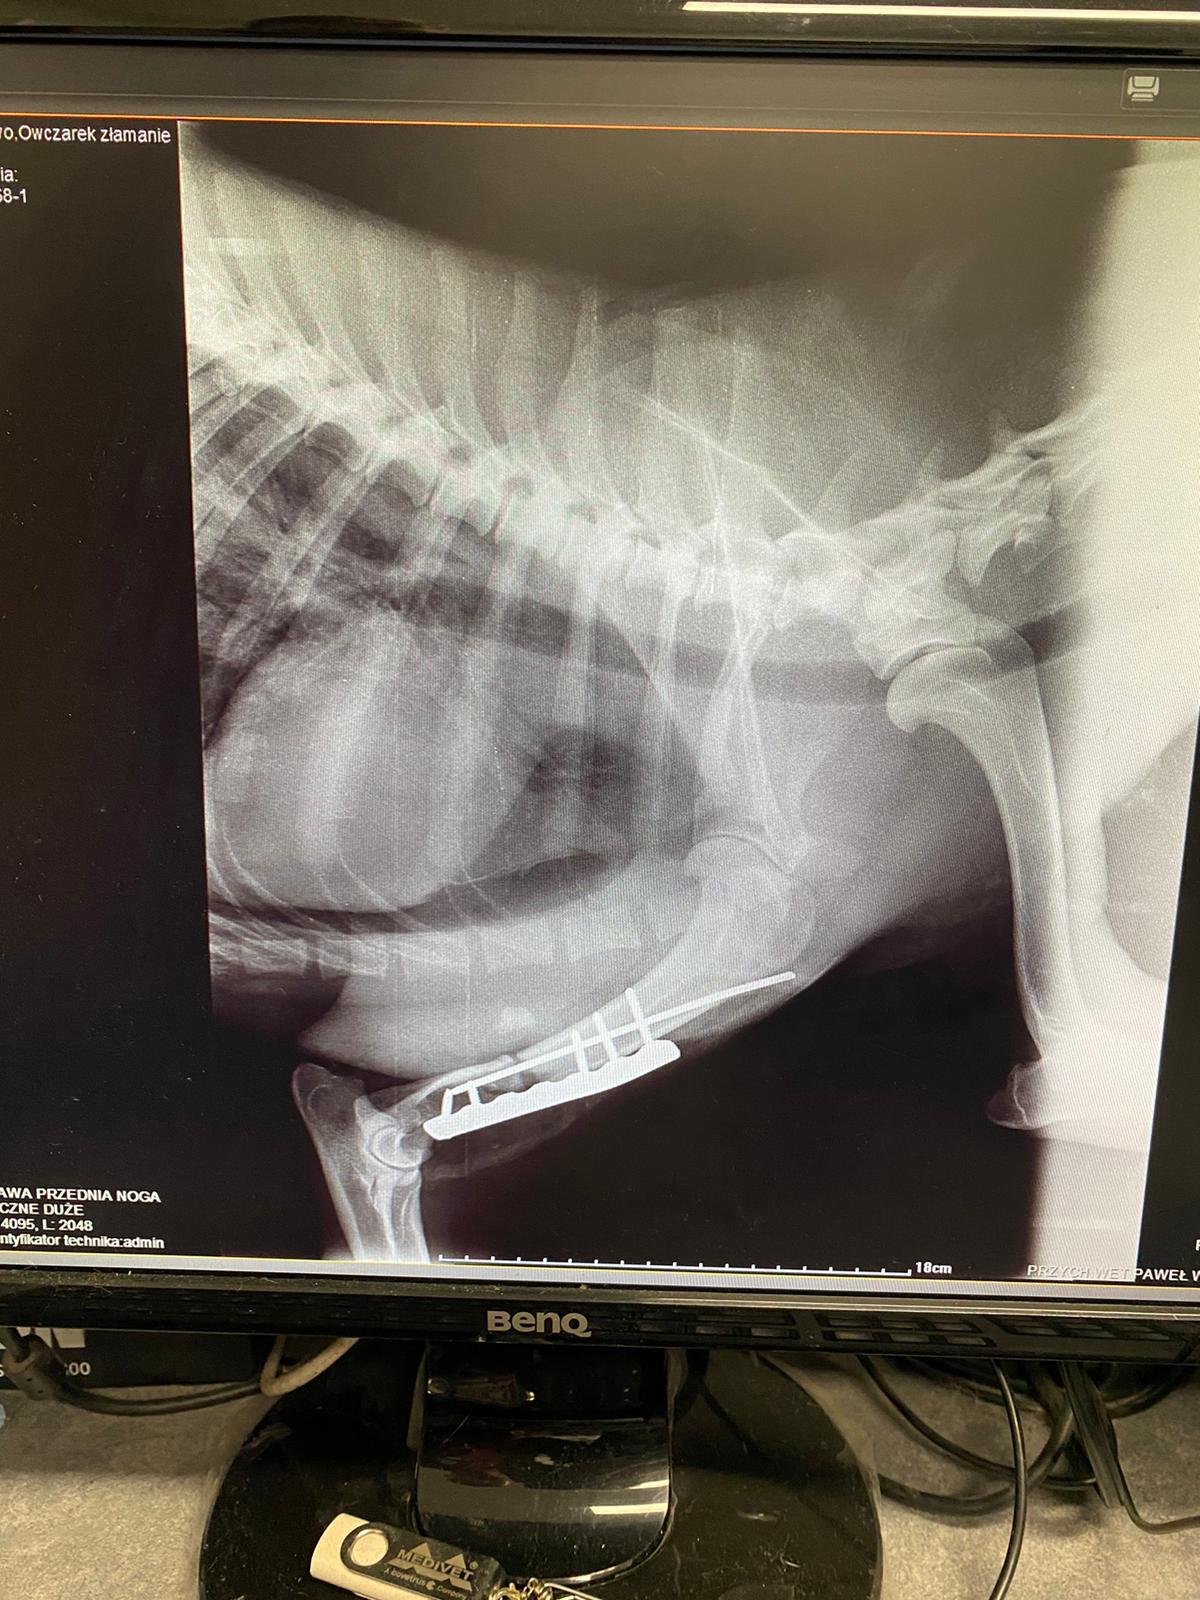

2-letni owczarek niemiecki, który wabi się Tytus został znaleziony na drodze przez młodego, empatycznego człowieka. Jest w trakcie leczenia skutków wypadku. Zostało zrobione RTG, które wykazało złamanie kości ramiennej, przedniej łapy oraz obu łopatek.

Pies obecnie jest po operacji, która przebiegła pomyślnie. W ciągu kilku dni pies powinien był podjąć próbę wstawania, niestety tak się nie stało. Tytus z dnia na dzień zaczął czuć się coraz gorzej.

Pies obecnie jest po operacji, która przebiegła pomyślnie. W ciągu kilku dni pies powinien był podjąć próbę wstawania, niestety tak się nie stało. Tytus z dnia na dzień zaczął czuć się coraz gorzej.

Zgodnie z zaleceniami lekarza weterynarii należy wykonać rezonans, gdyż mogło dojść do uszkodzenia rdzenia kręgowego. Jest nam przykro, ponieważ robimy wszystko, co w naszej mocy, aby życie Tytusa wróciło do normy. Prosimy o wsparcie.